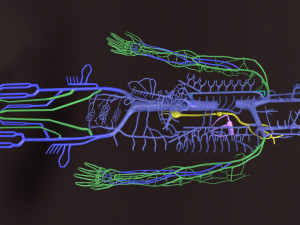

The model meshes include adult circulation versus circulation in Tetralogy of Fallot (TAF), arrow labels and text labels. The blood flow in a patient with Tetralogy of Fallot is outlined in this model. To contrast it to normal blood circulation a separate model of normal circulation is included. The Tetralogy of Fallot (OVER RIDING OF AORTA, PUL STENOSIS, VENTRICULAR SEPTAL DEFECT, RIGHT VENTRICULAR HYPERTROPHY), fossa, ligament teres , venosus, and arteriosus are duly depicted with proper labelling and blood flow directional arrows. Excellent model for teaching, demonstration and knowlegde of human body. The models include both procedural and image textures blend files separately. The texture file include diffuse, roughness and normal png and jpeg based on non overlapping UV maps.